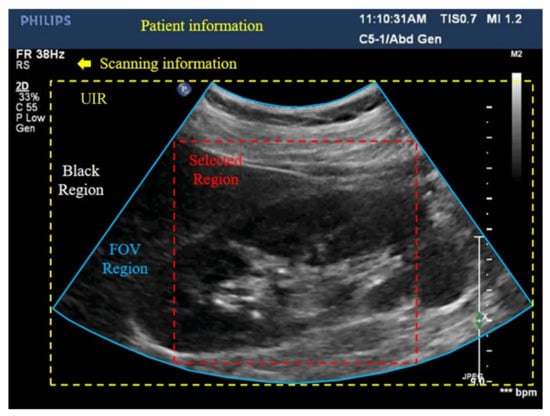

2.1. Reverse Scan Conversion